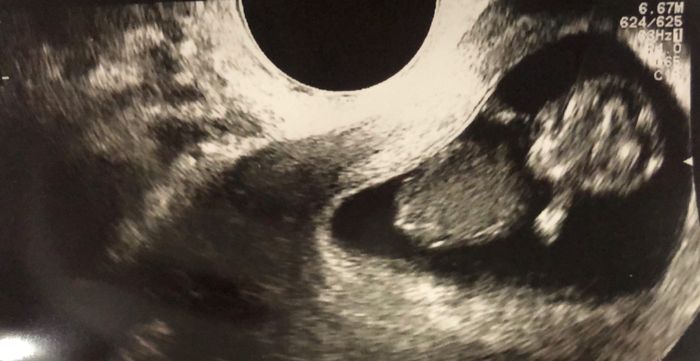

Altra domandina: l’11 ho fatto il dna fetale (con Nativa) e mi hanno detto che se entro 7 giorni non mi fanno sapere nulla di chiamare, ma secondo voi devo calcolare i sabati e le domeniche? Così il tempo si allunga e questi giorni sembrano non passare mai 😓😓 grazie a tutte quelle che capiranno la

mia ansia 😂😂